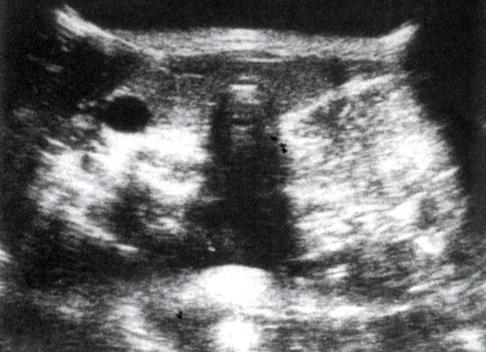

На снимке УЗИ

Признаки заболевания на УЗИ:

- уплотнение ограничено и заключено в плотную капсулу;

- липома на УЗИ имеет овальную форму;

- гипоэхогенная структура, возможно, включение фиброзных тяжей, кристалликов кальция;

- при надавливании поддается сжатию;

- межмышечные опухоли располагаются вдоль фасциальных плоскостей между мышечными волокнами;

- акустические эффекты;

- изменения в ближайших лимфоузлах.

После осмотра и диагностики пациент получает на руки описание выявленного образования. УЗИ помогает определить жировик по параметрам: размер, форма, тип – узловой или диффузный, наличие компрессии соседних органов.

3. При ультразвуковом исследовании (УЗИ) липомы имеют вид гипоэхогенных образований с тонкой капсулой, располагающихся в толще жировой ткани.